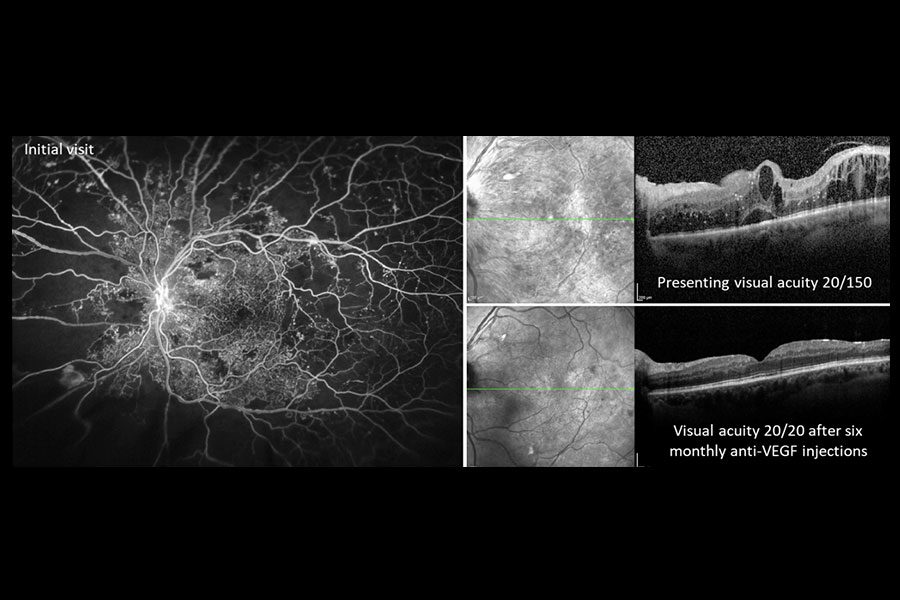

| Figura 4. Imagen de angiografía con fluoresceína de campo amplio del ojo derecho de un paciente con retinopatía diabética proliferativa, que muestra áreas hiperfluorescentes de tinción vascular y fuga junto con áreas hipofluorescentes de no perfusión capilar. Foto: Jason Hsu, MD. |